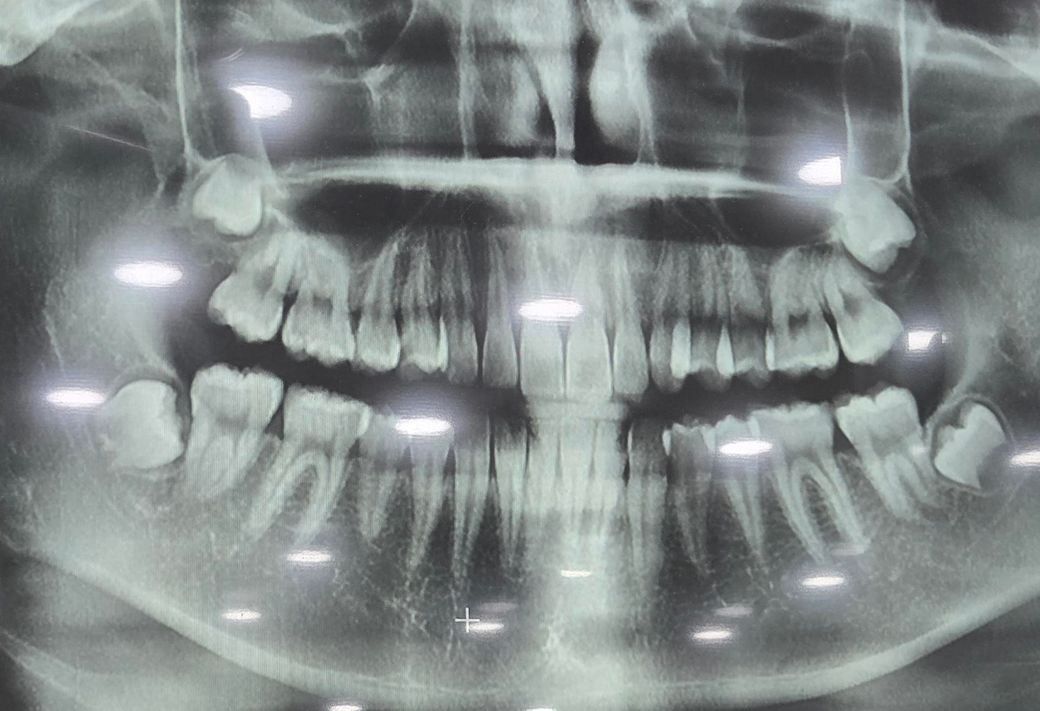

제가 10월에 어금니 통증도 있고 아래 쪽 끝 어금니 부분에 잇몸이 달랑거여서 병원에 방문하였고 X-레이를 찍었는데 사랑니가 다 있지만 괜챃다고 자라나고 있다고 하더라구요 또한 위쪽 왼쪽 어금니 통증이 있긴했지만 그때는 많이 아프지도 않고 가끔 아픈 거라 그런가보다 하고 넘겼는데 현재 위쪽 왼쪽 어금니 통증이 심해요ㅠ 끝 어금니와 옆에 있는 어금니 사이가 혓바닥으로만 해도 아프고 왼쪽 끝 어금니 부분에 있는 잇몸 끝을 혓바닥으로 만져보면 어금니 치아모양이 느껴집니다. 하지만 제가 봤을 때 잇몸의 더 이상의 자리가 없고 자라나더라도 옆으로 자라나거나 볼을 씹을 거 같은데 계속 자라나게 둬도 괜찮은 건가요? 그리고 잇몸 부분이 반대쪽에 비해 부어있어요!

• 1번 째 사진